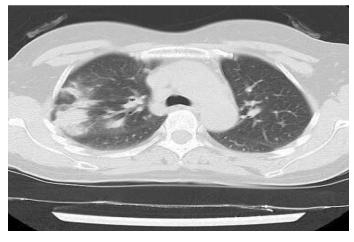

下面这个患者,右下叶病灶,既无磨玻璃,又不在胸膜下,依靠CT诊断新冠肺炎几乎不可能。

影像学鉴别

诊断一个疾病,从来都是需要医生综合分析,特别是对于广大基层医院,单纯依靠影像学发现新冠肺炎,十分困难。很多疾病都可以表现为胸膜下为主的病灶。